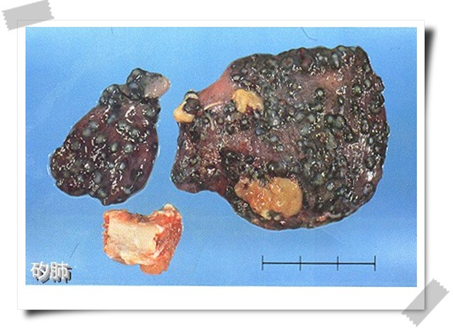

矽肺病例尸检肉眼观察,可见肺体积增大,晚期肺体积缩小,一般含气量减少,色灰白或黑白,呈花岗岩样。肺重量增加,入水下沉。触及表面有散在、孤立的结节如砂粒状,肺弹性丧失,融合团块处质硬似橡皮。可见胸膜粘连、增厚。肺门和支气管分叉处淋巴结肿大,色灰黑,背景夹杂玉白色条纹或斑点。

矽肺

矽肺的基本病理改变是矽结节形成和弥漫性间质纤维化,矽结节是矽肺特征性病理改变。矽肺病理形态可分为结节型、弥漫性间质纤维化型、矽性蛋白沉积和团块型。